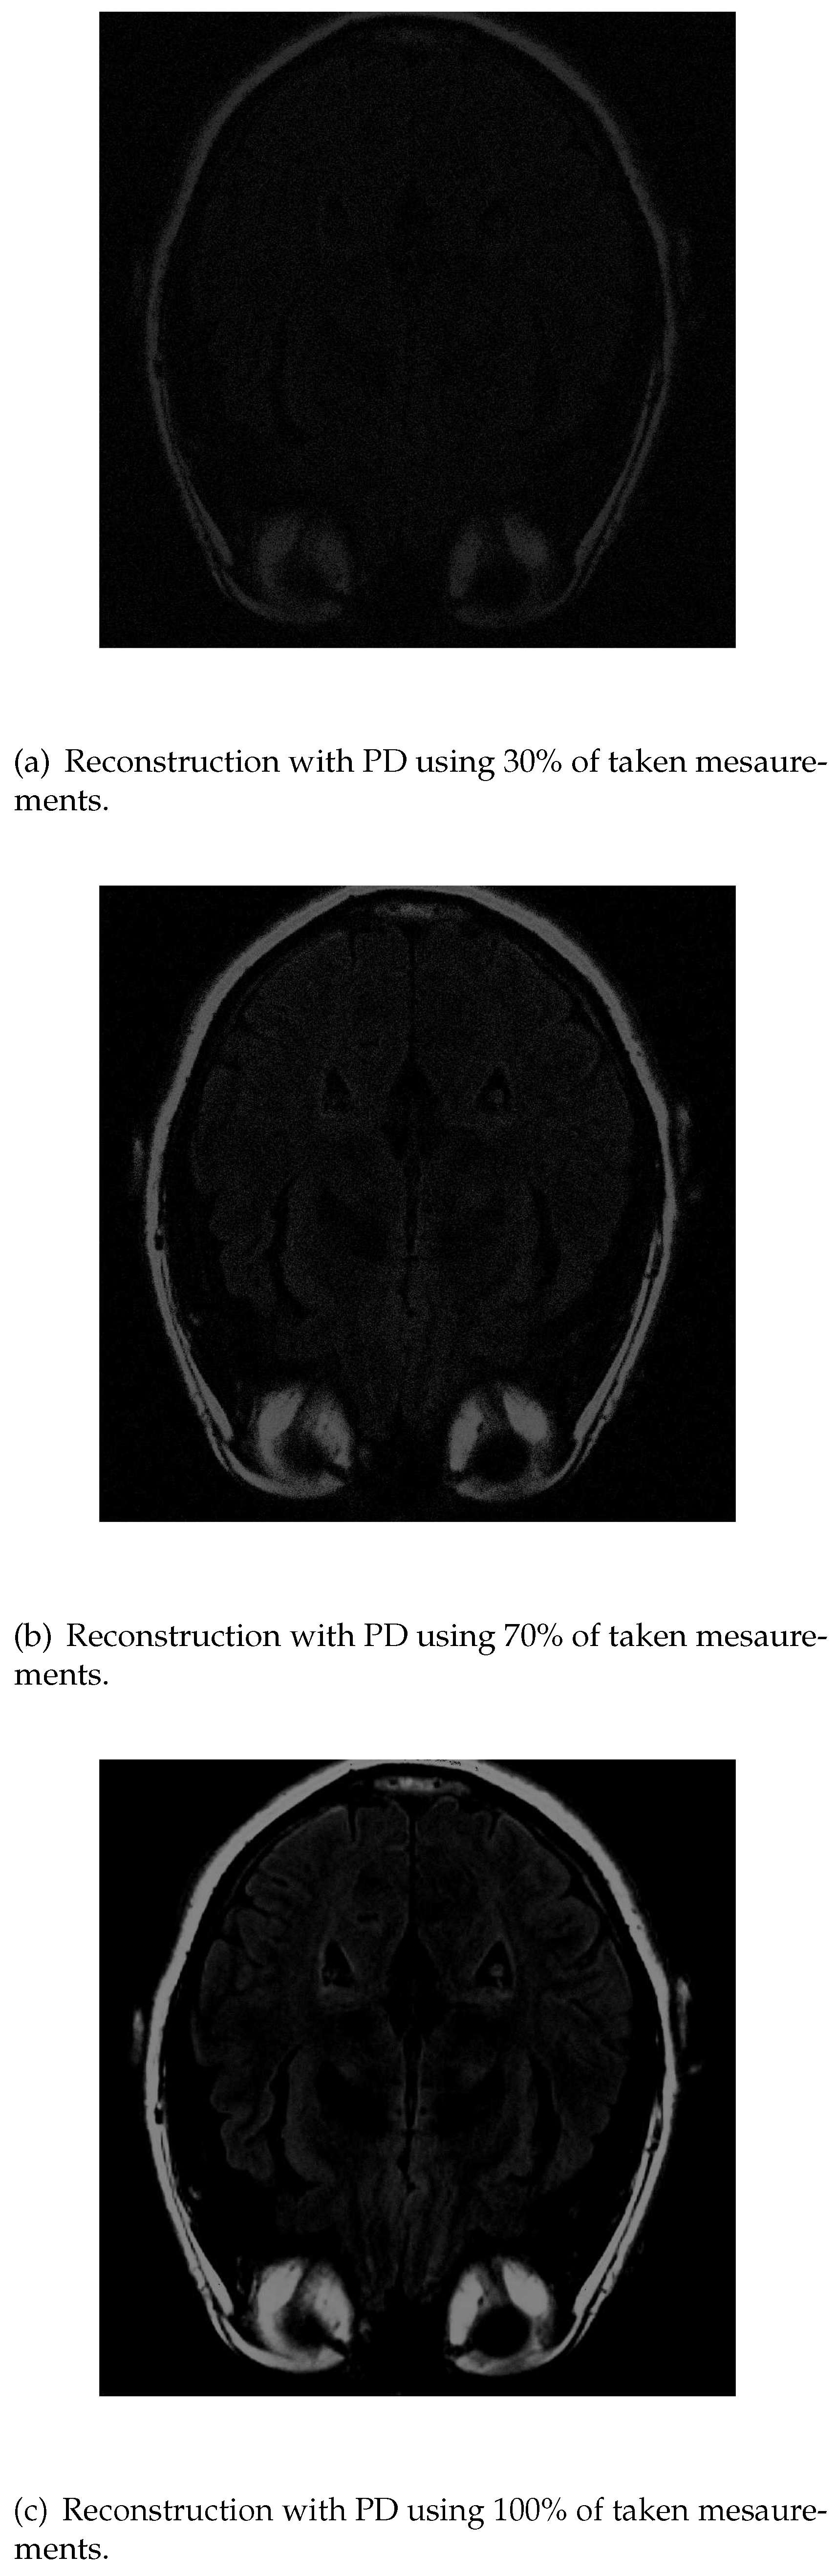

If we apply PD algorithm the object is much clearer with lower measurements. When it is used 30% of the initial values Figure 8a), the structure inside the head can be recognized and delimited, even though its low intensity. As the number of measurements is increased, the images get better resolution so when we have 70% Figure 8b), the image is similar to the original one. Finally, with 100% Figure 8c), the grey matter loses its intensity.

Figure 8. Reconstruction of the image in Figure 3 using PD with 30 % (a), 70 % (b) and 100 % (c) of taken measurements.